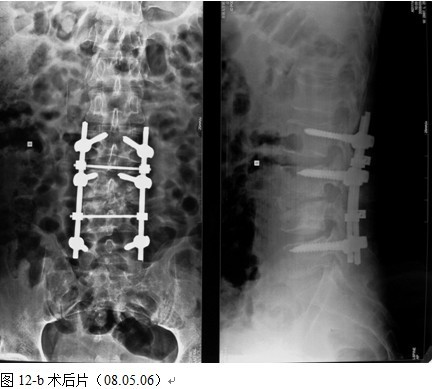

本组手术用时间3~4h , 平均3.5h 。术中出血300~500ml , 平均约350ml 。术后症状完全缓解,无神经功能障碍加重等并发症,1例营养差的老年患者伤口出现窦道,1例因肝功能差,术后未口服抗痨药,伤口出现窦道,经换药后二期愈合,其余病例伤口均一期愈合。马尾神经受损的患者术后基本恢复正常。术后一周后凸角平均 5.4°后凸畸形平均矫正90%以上, 最终后凸角平均8.3°,后凸角度平均丢失4.2°。随访3个月有87%(40/46)有骨痂形成,6个月91.3%(42/46)明显骨性愈合(见图),其余4例9-12个月内愈合,随访时间3-32个月,平均11个月,46例患者中2例在术后2个月和3个月时背部形成脓肿,换药后治愈。2例出院1月后并发结核性脑膜炎,治疗后好转。1例因椎弓根钉偏外,刺激神经根,5个月后从侧方脱出,疼痛加重,因前后路植骨完全愈合,取出后症状完全缓解。

中国学者金大地[22]等采用一期前路病灶清除植骨前路钢板固定治疗腰椎结核,平均18°的后凸畸形得以矫正,Mukhtar[23] AM等采用前路病灶清除植骨分期或同期后路固定治疗腰椎结核22例,术后后凸畸形矫正度数平均为27°。从我们的随访结果看,术后后凸畸形平均矫正度数为26.9°,后凸畸形平均矫正90%以上, 6个月-49个月后随访,后凸角度平均丢失4.2°。本术式也适用于结核所引起的弹性差的后凸畸形,对于病灶纤维化或骨化的非弹性后凸畸形,后路固定后,先行前路病灶、纤维化或骨化切除、松解,逐步刮除病灶、逐步撑开,达到畸形矫正和植骨的目的。